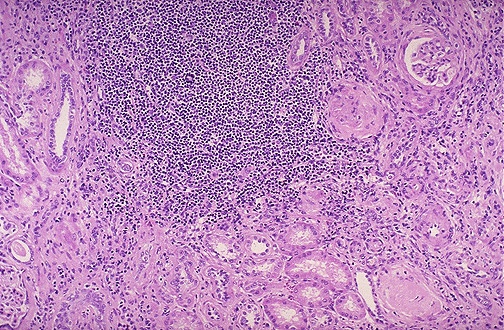

Image 5.3

At low power, the adjacent kidney shows chronic inflammation microscopically.